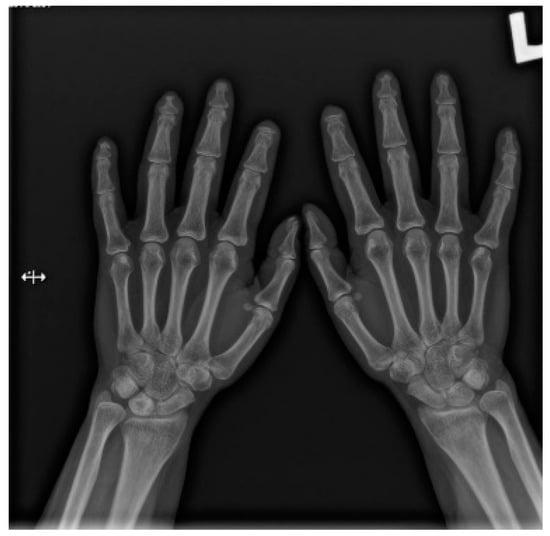

Hands are the most characteristic location of lesions in SSc. Articular symptoms are seen in 10–60% of patients at the time of diagnosis. Features allowing to distinguish changes caused by scleroderma from symptoms of other diseases are predominantly acro-osteolysis, calcifications, and soft-tissue thinning, which are all visible on radiographs [13]. According to the latest research, acro-osteolysis (Figure 1 and Figure 2) is seen in about 16% of patients [14]. The distinctive ‘sharpened pencil’ sign is caused by resorption of the terminal tuft of distal phalanges; this symptom is usually more pronounced on the palmar surface of phalanges. A correlation between acro-osteolysis and digital ulcerations was observed. The less common locations where bone resorption might be seen in SSc patients include medial parts of the ribs, distal end of the radial and ulnar bones, clavicle, and mandibulum [15,16]. Although acro-osteolysis is a common finding in SSc, a number of other pathological entities might be also associated with this symptom—including rheumatological disorders, psoriatic arthritis, hyperparathyroidism, and thermal injuries [17,18].

Figure 2.

A-P view of the hand radiograph in a patient with systemic sclerosis shows acro-osteolysis of the distal phalanx of the first, second, third, and fourth fingers of both hands. Additionally, small joint contractures and areas of calcinosis in the fingertips are visible.